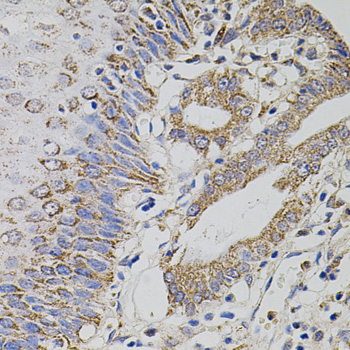

Facts about tRNA (uracil-5-)-methyltransferase homolog A.

| Gene Name: | Trmt2a |

| Uniprot: | Q8BNV1 |

Widely expressed at low level. Expressed at higher level in proliferating cells.